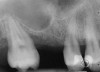

A 55-year-old male was referred for implant placement and prosthetic rehabilitation in the area of tooth No. 15. The tooth had been extracted 4 years prior. The radiograph revealed inadequate bone height for implant positioning (Figure 6). It was decided to insert an implant that was 11.5 mm in length and 3.75 mm in diameter, performing a slight osteotomic maxillary sinus lift. A heterologous bone graft also was planned to obtain a larger sinus lift.

A full-thickness mucoperiosteal flap was raised, and alternating osteotomes were used to prepare the implant site. After achieving a length of 7 mm (Figure 7A and Figure 7B), heterologous bone graft was implanted and the osteotome sequence was repeated. The implant showed primary stability.

Second-stage surgery was performed after 4 months (Figure 8); healing abutments were placed and the soft tissue was allowed to heal for 5 more weeks. Then, splinted porcelain-fused-metal (PFM) crowns supported by custom gold abutments were delivered (Figure 9 and Figure 10).

Figure 6 Preoperative radiograph of the area around tooth No. 15.

Figure 8 At 4 months after treatment, the radiograph revealed the presence of a bone layer surrounding the implant.